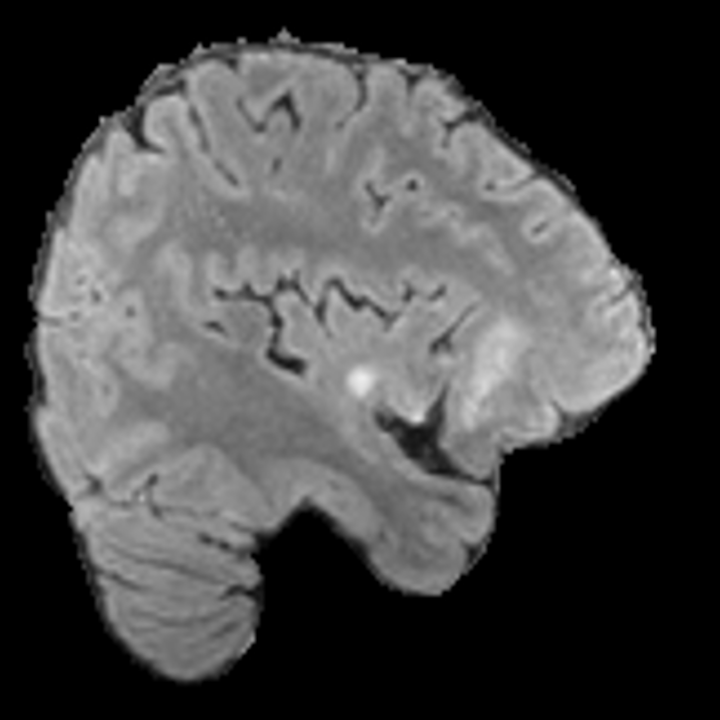

Our results unequivocally highlight the superior performance of X-Diffusion in terms of both qualitative and quantitative metrics. Representative MRI volumes generated by our pipeline, when juxtaposed with ground-truth images, showcased remarkable similarity, with even intricate physiological features like tumor information, spine curvature, and fat distribution being accurately captured.

Notably, X-Diffusion achieves sota dB for a few input slices while baselines require more than 60 input slices to achieve similar performance (Figure 7). The margin is more than 12 dB PSNR for the 1-slice input in both the BRATS and the UK Biobank benchmarks (see Table 1 and Figure 6). For reference, two randomly sampled MRIs from the UK Biobank would have a PSNR of 15.95 dB 0.36 (on 4800 randomly sampled examples). The slices from 3D reconstructed volumes at varying depths and axis of rotation visually match the ground truths (see Figures 5 and Figure 4). We also plot the error map (Figure 4) of such X-Diffusion generations to highlight the differences with the ground truth MRIs.

Preservation of Spine Curvature. For the spine segmentation on UK Biobank, we use a UNet++ model [81] with Dice Loss and use the curvature prediction of the spine followed in [9]). We measure the Pearson correlation factor [9] of spine curvature measured on the generated MRIs where the input is a single MRI coronal slice, or a single sagittal slice against the curvature of reference real MRIs of the same samples. The correlation coefficients are 0.89 for the coronal MRIs and 0.88 for the sagittal MRIs on the test set of 308 human-annotated angles.

B.3 Preservation of Spine Curvature and Fat

For the spine segmentation on UK Biobank, we use a UNet++ model [81] with Dice Loss. We use a model trained to predict curves on DXA on UK Biobank [9]. We show in Figure 20 that generated MRIs preserve the spine curvature from normal to severe scoliosis cases. We also study the case when DXA is used to generate the MRIs and show in Figure 14 how the correlation to real curvatures compares to the input MRI case. The curvatures of the MRI generated from the coronal plane match the DXA curvatures more than the curvatures generated from sagittal MRI. This is expected since the antero-posterior plane of DXA is equivalent to the coronal plane for MRIs. This also explains the greater Pearson’s correlation coefficient of the coronal MRI (0.89) and DXA-generated curvature (0.88) compared to sagittal-generated curvature (0.87) relative to the reference curvature on the coronal plane. We observe though that MRI generation using X-Diffusion from another plane than the conventional plane for scoliosis assessment is valid.

D.4 Spine Curvature Analysis

For the spine segmentation on UK Biobank, we use a UNet++ model [81] with Dice Loss. We use a model trained to predict curves on DXA on UK Biobank [9]). We measure the Pearson correlation factor [9] of spine curvature measured on the generated MRIs where the input is a single MRI coronal slice, a single sagittal slice, or from the paired DXA, against the curvature of reference real MRIs of the same samples. The correlation coefficients are 0.89 for the coronal MRIs, 0.88 for the sagittal MRIs, and 0.87 for the DXAs on the test set of 308 human-annotated angles. We can then bin the curvature, , of the spines under different scoliosis categories based on human-annotated angles: mild: , moderate: , and severe . We show the results in Figure 20. This illustrates that the generated MRIs preserve the spine curvature from normal to severe scoliosis cases.